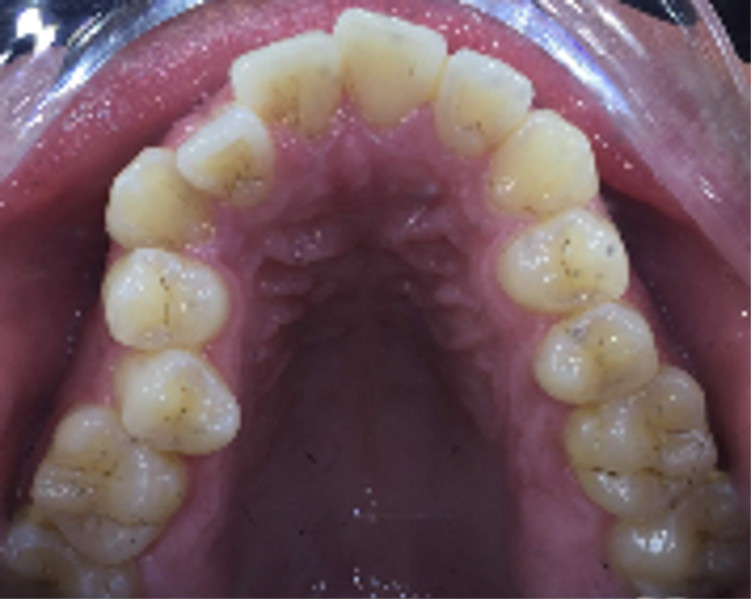

The patient presented with the goal of enhancing her smile. She had a narrow smile, bilateral posterior crossbite and an anterior crossbite with tooth #12. From the extra-oral perspective, the patient was also wider on the right vertical fifth (Figs. 25–28). The treatment objective was to correct the anterior crossbite and posterior crossbite and to simultaneously correct the asymmetrical buccal corridors by further broadening the arch on the right more than the left. Once the alignment had been completed, the case was finished with in-chair tooth whitening and composite augmentation of teeth #12 and 22 (Figs. 29–31).

Fig. 27: Occlusal view of the maxillary arch.

Fig. 28: Orthodontic digital simulation using Invisalign software to show the pre-treatment position (blue) and the predicted result after treatment (white).